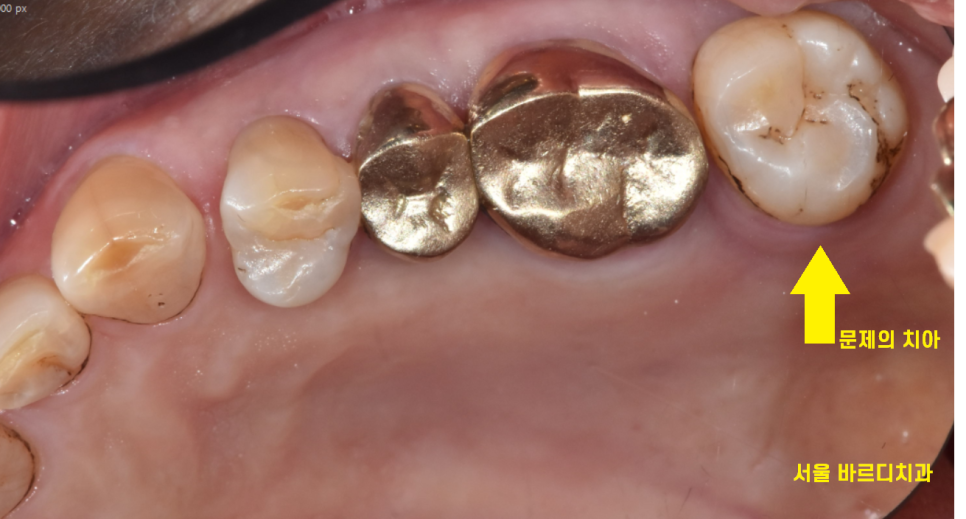

오래전에 한 보철이 벗겨져서

고덕동 치과 내원하셨습니다.

안쪽이 충치로 다 부서지고 깨져서

뽑을 수 밖에 없었는데요.

뽑는 김에 뒤에 흔들리는 치아도 같이 뽑고

고덕동 임플란트를 해야하는 상황

어금니 2개나 뽑았으니 치료가 필요했습니다.